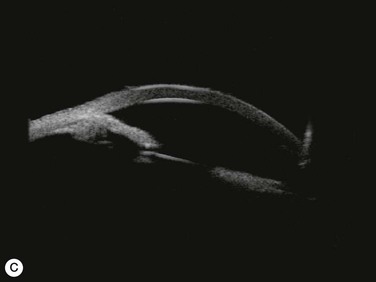

Several studies have shown that extracapsular cataract extraction (ECCE) with IOL implantation is effective in opening the angle and controlling IOP in refractory PAC.27–30 Currently, ECCE has been replaced by phacoemulsification which offers a higher surgical success rate, less postoperative inflammation and fewer complications. In addition, the clear corneal approach spares the superior conjunctiva for possible filtering surgery, if needed. Phacoemulsification and IOL implantation has been reported to be highly effective in patients with uncontrolled PAC.31,32 However, up to 32% of the patients still had persistent PAS and required long-term treatment with glaucoma medication following lens removal either by ECCE or phacoemulsification and IOL implantation alone (Fig. 108-2A).5,32 Goniosynechialysis is the next step to eliminate the remaining synechiae and control the IOP (Fig. 108-2C).

Goniosynechialysis becomes more effective when performed after lens removal. An increase in the anterior chamber space provides ample room to perform the procedure and reduces the chance of synechial reformation. Combined phacoemulsification and GSL (phaco-GSL) has been shown to be safe and highly effective in controlling IOP (<21 mmHg) and decreasing PAS in >90% of 52 eyes that developed acute PAC within 6 months and had persistent IOP elevation following laser treatment.26,33,34 Postoperative IOP was reduced to below mid-teens regardless of the preoperative IOP level. Recurrence of the PAS, although uncommon, might occur during the first three months. The success of phaco-GSL has been stable since the third postoperative month for up to 14 years, providing a long-lasting control or even a permanent cure.26 A recent multicenter study also demonstrates a success rate (< 21 mmHg) of 85.9% in 109 eyes with uncontrolled PAC/PACG at one and three years following phaco-GSL.35

Patients are treated with antiglaucoma medications and frequent topical steroids. When the inflammation subsides, the medications are then slowly tapered off within a month. Occasionally, a release of aqueous through the paracenteses at the slit lamp may be performed if a high IOP rise occurs. Gonioscopy typically reveals opening of the angle structures with irregular pigmentation on the newly exposed trabecular meshwork and the angle wall (Fig. 108-6). Angle recession or a cyclodialysis cleft are undesirable findings. If successful, anterior segment optical coherence tomography or ultrasound biomicroscopy should demonstrate separation of the PAS and reopening more than half of the entire angle (Figs 108-2, 108-7).